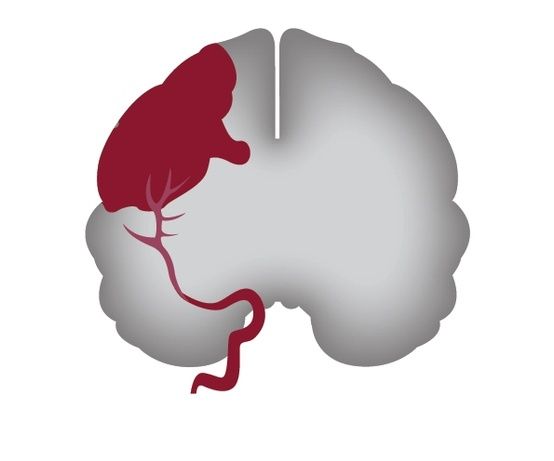

Μια τεχνική που αφορά απευθείας έγχυση ενός φαρμάκου στον εγκέφαλο ασθενών με αιμορραγικό εγκεφαλικό δίνει ελπίδα απομάκρυνσης θρόμβων ακόμη και με μέγεθος όσο αυτό μιας μπάλας του γκολφ! Αυτό ανέφεραν ερευνητές της Ιατρικής Σχολής του Πανεπιστημίου Τζονς Χόπκινς στη Βαλτιμόρη κατά τη διάρκεια διεθνούς συνεδρίου για τα εγκεφαλικά επεισόδια της Αμερικανικής Καρδιολογικής Ενωσης οι εργασίες του οποίου ολοκληρώνονται σήμερα στη Χονολουλού της Χαβάης. Σύμφωνα με τους ειδικούς, η νέα μέθοδος φαίνεται να είναι ασφαλής και μπορεί επίσης να μειώσει τη μακροπρόθεσμη αναπηρία των συγκεκριμένων ασθενών.

Στο πλαίσιο διεξαγωγής της θεραπείας οι χειρουργοί ανοίγουν μια οπή με μέγεθος όσο εκείνο ενός μικρού κέρματος στο κρανίο του ασθενούς. Περνούν στη συνέχεια μέσα στον εγκεφαλικό ιστό έναν καθετήρα, ο οποίος και φθάνει ως το μεγαλύτερο σημείο του θρόμβου που έχει σχηματιστεί στον εγκέφαλο μετά το αιμορραγικό επεισόδιο.

Μέσω του καθετήρα οι ειδικοί εγχέουν το θρομβολυτικό φάρμακο που ονομάζεται ανασυντεθειμένος ιστικός ενεργοποιητής του πλασμινογόνου (rtPA) στον εγκέφαλο. Η έγχυση γίνεται κάθε οκτώ ώρες επί περίπου τρεις ημέρες και στο τέλος αυτού το διαστήματος ο θρόμβος απομακρύνεται μέσω του καθετήρα.

Η μέθοδος δοκιμάστηκε από τους ερευνητές του Τζονς Χόπκινς σε 96 ασθενείς από 26 νοσοκομεία οι οποίοι είχαν υποστεί αιμορραγικό εγκεφαλικό επεισόδιο (αυτού του είδους το επεισόδιο προκαλείται λόγω ρήξης μιας αρτηρίας στον εγκέφαλο η οποία στη συνέχεια αιμορραγεί).